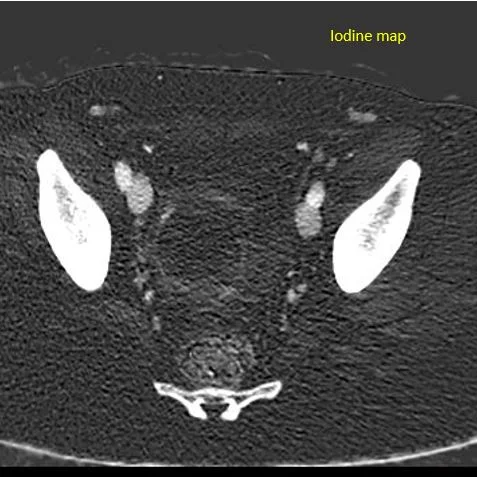

Iodine map: No uptake in the mass. Notice the thin enhancing margin. This is a blood clot inside a cyst.

Iodine map: See perfusion to the uterus, and absent perfusion posterior, c/w clot.